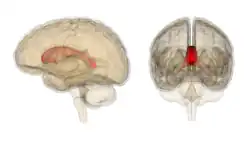

The corpus callosum (Latin for "tough body"), also callosal commissure, is a wide, thick nerve tract, consisting of a flat bundle of commissural fibers, beneath the cerebral cortex in the brain. The corpus callosum is only found in placental mammals.[1] It spans part of the longitudinal fissure, connecting the left and right cerebral hemispheres, enabling communication between them. It is the largest white matter structure in the human brain, about 10 cm (3.9 in) in length and consisting of 200–300 million axonal projections.[2][3]

A number of separate nerve tracts, classed as subregions of the corpus callosum, connect different parts of the hemispheres. The main ones are known as the genu, the rostrum, the trunk or body, and the splenium.[4]